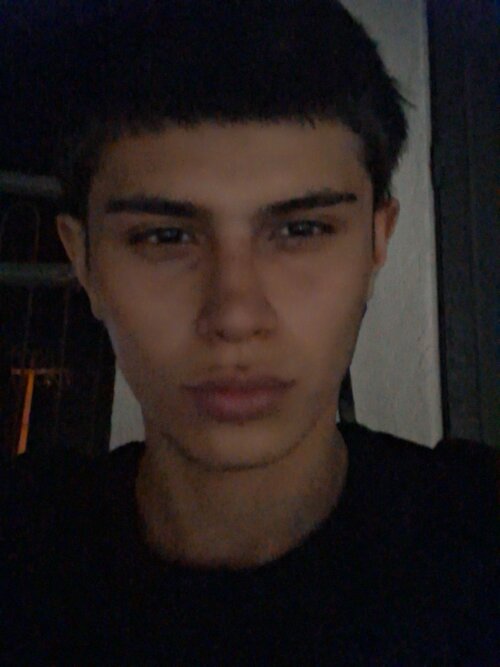

Hi everyone, how are you? I have facial asymmetry — my right side is more drooped/weaker. I won’t drag this out, so I’ll list a few symptoms:

I feel like the right side of my palate is slightly higher, while the left side is slightly lower and wider. I also feel that my lower second molar is a bit inward (when I touch it with my tongue). I probably have bruxism as well — when I open my mouth wide, I notice a difference in my TMJ movement, especially on the right side.

I also feel like my lower teeth are more inward (I’m not sure how to explain it exactly). I’d like to know the best way to fix this. I’ll send some photos and my cephalometric analysis, If you could please use simpler English, I would appreciate it, as I am Brazilian and it's difficult to translate(Note: I also feel a slight muscular difference when touching my face.)

I feel like the right side of my palate is slightly higher, while the left side is slightly lower and wider. I also feel that my lower second molar is a bit inward (when I touch it with my tongue). I probably have bruxism as well — when I open my mouth wide, I notice a difference in my TMJ movement, especially on the right side.

I also feel like my lower teeth are more inward (I’m not sure how to explain it exactly). I’d like to know the best way to fix this. I’ll send some photos and my cephalometric analysis, If you could please use simpler English, I would appreciate it, as I am Brazilian and it's difficult to translate(Note: I also feel a slight muscular difference when touching my face.)